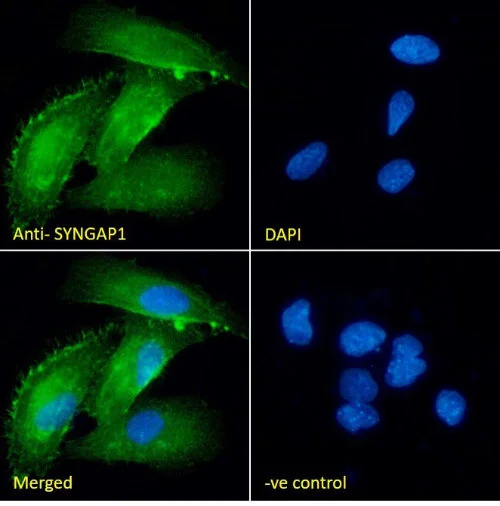

| EB11147 | Goat Anti-SYNGAP1 (aa1169-1183) Antibody | Pep-ELISA, WB, IHC, IF | Human, Mouse, Rat, Dog, Pig, Cow | 100µg/200µl |